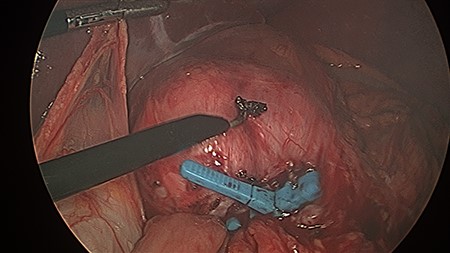

The patient was positioned supine, and cut down entry periumbilically was performed with a 10-mm camera port and two 5-mm working ports inserted. On laparoscopy, a retrograde intussusception with the intussuscipien constituted the gastric pouch and the intussusceptum constituting the alimentary limb of the jejunum was identified. Just distal to the intussusceptum, there was a jejunal mesenteric defect, with demonstrable thinning of mesenteric fat and various tears. Through this defect, the remnant stomach, normally situated on the left side of the gastric pouch, was found to have herniated from the left to right through this jejunal mesenteric defect, posterior to the alimentary limb in the supracolic compartment. This internal hernia was reversed and the defect closed with non-dissolvable V-Loc™ barbed sutures. A slipped MiniMizer gastric ring was then identified 3 cm distal to the gastrojejunal anastomosis (Fig. 2). No fixation sutures were identified. On release of the ring, 25 cm of alimentary limb jejunum was, with gentle traction, pulled from its invagination into the gastric pouch through where the ring was originally placed (Fig. 3). Surprisingly, all bowel was viable and no resection was required.

The MiniMizer ring has been removed. Alimentary limb jejunal intussusception and left to right remnant stomach herniation can be appreciated. Gentle traction on the intussusceptum resulted in 25 cm of viable bowel pulled from the invagination.